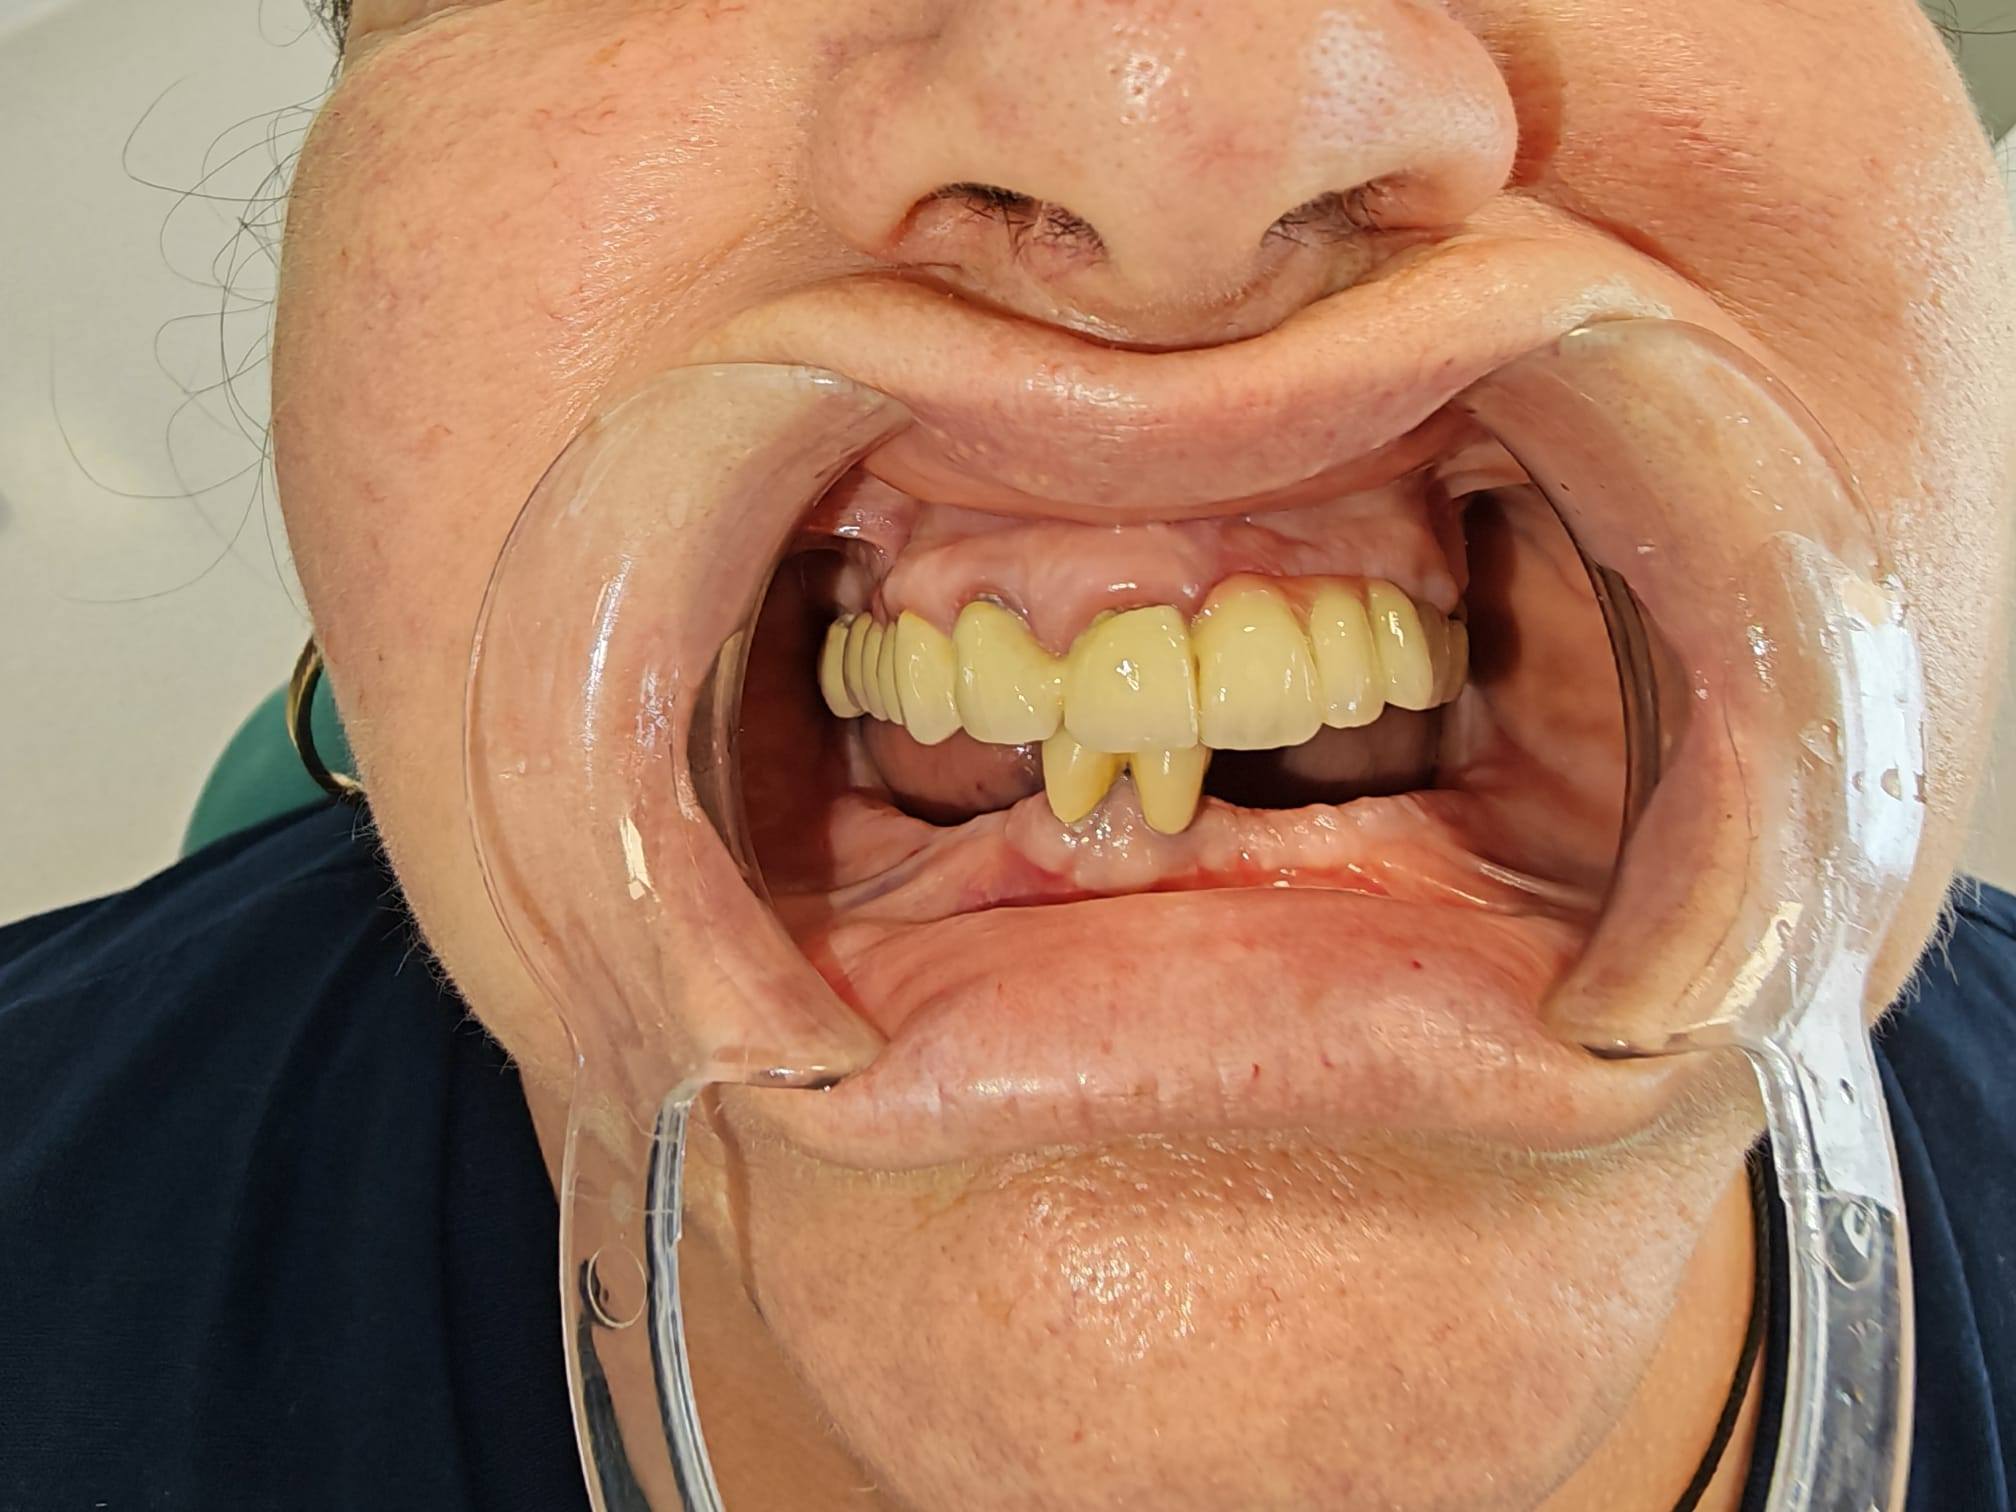

Pacientul s-a prezentat cu o situație clinică ce necesita o soluție fixă, stabilă și estetică pentru arcada inferioară (mandibulă). Alegerea terapeutică a fost o procedură de tip All-on-X cu încărcare imediată. Acest concept permite pacienților să plece din clinică cu dinți ficși temporari în doar 24 de ore de la intervenție, eliminând disconfortul protezelor mobile tradiționale.

Rezultat Estetic și Funcțional Imediat: Recuperarea funcției masticatorii și a încrederii în sine într-un timp record.

Acest caz clinic prezentat de Cabinete Rx Dentis Târgu Frumos subliniază standardul ridicat al stomatologiei moderne din regiune. Prin combinarea experienței chirurgicale cu sisteme digitale precum Scan LogiQ, reabilitările complexe devin proceduri sigure, rapide și extrem de durabile.